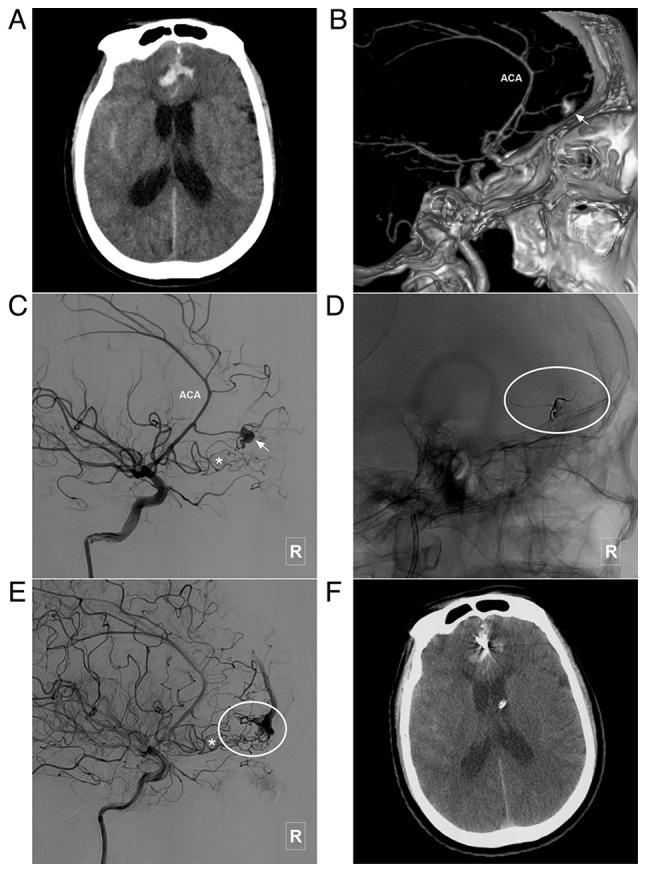

To date, at least to the best of our knowledge, there are only limited studies available on the endovascular treatment (EVT) of brain arteriovenous malformations (BAVMs) involving the anterior cerebral artery (ACA), thus termed ACA-BAVMs. The present study retrospectively examined 60 patients with ACA-BAVMs treated with EVT. The patients were aged between 10 and 72 years (mean age, 35.4±7.0 years) and included 28 females (46.7%, 28/60). The ACA-BAVMs were divided into three types: Type I BAVMs were those located below and in front of the corpus callosum genu, type II BAVMs were those located at the upper area of the corpus callosum from the genu to the anterior portion of corpus callosum body, and type III BAVMs were those located from the anterior portion of corpus callosum body to the splenium of the corpus callosum. There were 9 (15%, 9/60), 15 (25%, 15/60) and 36 (60%, 36/60) patients with type I, II and III ACA-BAVMs, respectively. Statistical analysis revealed that the posterior cerebral artery (PCA) tended to be involved in type II and III BAVMs. All patients were treated using EVT. During EVT, there were 3 cases of intraoperative bleeding (5%, 3/60), which tended to occur in type I and II ACA-BAVMs. The other 57 cases (95%, 57/60) had no complications and new neurological deficits. At the time of discharge, 48 (80%, 48/60) patients had a Glasgow Outcome Scale score of 5. During the clinical follow-up period, 47 patients were classified according to the modified Rankin Scale (mRS) score; 39 (83%, 39/47) patients presented with an mRS score of 0. On the whole, the present study demonstrated that EVT may be a safe treatment for ACA-BAVMs.

迄今为止,至少就我们所知,关于累及大脑前动脉(ACA)的脑动静脉畸形(BAVM)的血管内治疗(EVT)的研究有限,因此称为ACA-BAVM。本研究回顾性分析了60例接受EVT治疗的ACA-BAVM患者。患者年龄在10至72岁之间(平均年龄35.4±7.0岁),其中女性28例(46.7%,28/60)。ACA-BAVM分为三种类型:I型BAVM位于胼胝体膝部下方和前方,II型BAVM位于胼胝体从膝部到胼胝体体前部的上部区域,III型BAVM位于胼胝体体前部到胼胝体压部。I型、II型和III型ACA-BAVM患者分别有9例(15%,9/60)、15例(25%,15/60)和36例(60%,36/60)。统计分析显示,大脑后动脉(PCA)在II型和III型BAVM中更易受累。所有患者均接受EVT治疗。在EVT过程中,有3例术中出血(5%,3/60),倾向于发生在I型和II型ACA-BAVM中。其他57例(95%,57/60)无并发症及新的神经功能缺损。出院时,48例(80%,48/60)患者的格拉斯哥预后量表评分为5分。在临床随访期间,47例患者根据改良Rankin量表(mRS)评分进行分类;39例(83%,3**********总体而言,本研究表明EVT可能是治疗ACA-BAVM的一种安全方法。